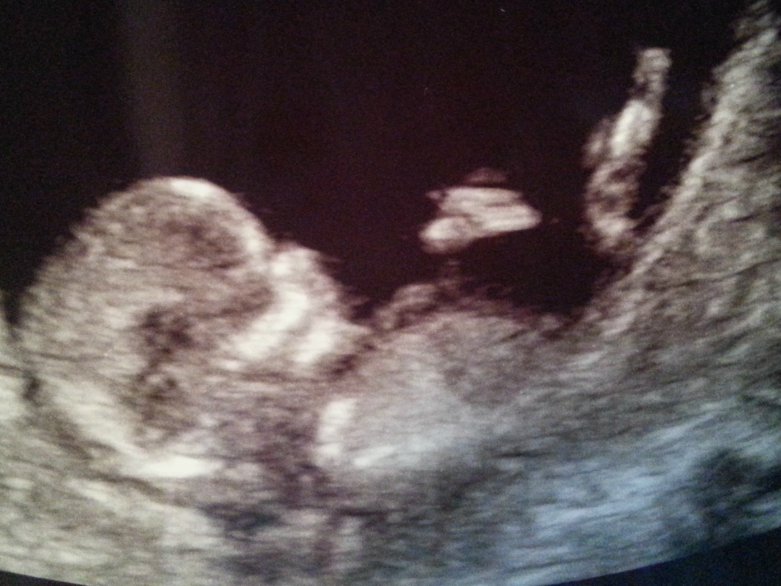

Vesta rv 13+4

Omia kuulumisia vähän: meillä on nyt kaksi ultraa takana ja masussa asustaa pieni ja vilkas Kung Fu -mestari. :Heartred Kerrottiin uutisetkin meidän perheille tällä viikolla ja vastaanotto oli ihan huikean ihana. Oma vointi on ollut hirmuisen hyvä aivan raskauden ensimmäisten viikkojen pahoinvointia lukuunottamatta, että nyt kun ultrat on todistanut että siellä on pikkuinen edelleen mukana, uskaltaa jo pikkuhiljaa alkaa nauttimaan olosta. Tai sitten vaan siirtyä stressaamaan seuraavaa asiaa :grin

Vesta, Ihana ultrakuva! Meidän 3,5v tunnisti myös kuvasta vauvan :) Tosin sekin voi vaikuttaa kun meillä on "unohtunut" jääkaapin oveen hänen omat ultrakuvansa niin saattaa olla, että mies on vaikka joskus kertonut niissä olevan vauva tms. Kiva kuulla, että raskaus on sujunut hyvin.

Vestalla ihania ultrakuulumisia, hienoa että siellä pikkuisella kaikki hyvin. Ajatella että sullakin jo noin hienot viikot kasassa, juurihan vasta plussasit :p

Vestalla ihana ultrakuva! <3

Ihanaa kuulla hyviä ultrakuulumisia Vesta! Ihana kuva! <3